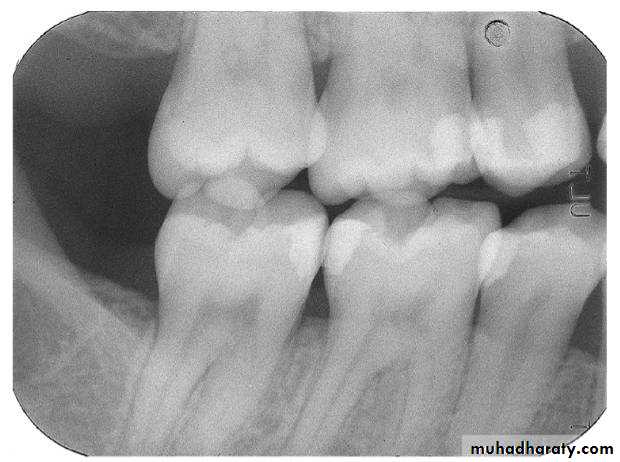

Bite-wing Radiography

• Indications:• Interproximal caries.

• Over-hang filling.

• Level of crestal bone between the teeth.

• Interproximal calculus.

• Principles:

• The film is placed in the mouth parallel to the crown of both upper & lower teeth.

• The film stabilized when the patient bites on the bite-wing tab or bite-wing film holder.

• The central ray of the x-ray beam is directed through the contacts of the teeth, using a +10 degree vertical angulation.

+10o vertical angulation is used to compensate for the slight bend of the upper portion of the film and the tilt of the maxillary teeth.

Premolar bitewing. A, Film placement. B, Resultant radiograph.

AB